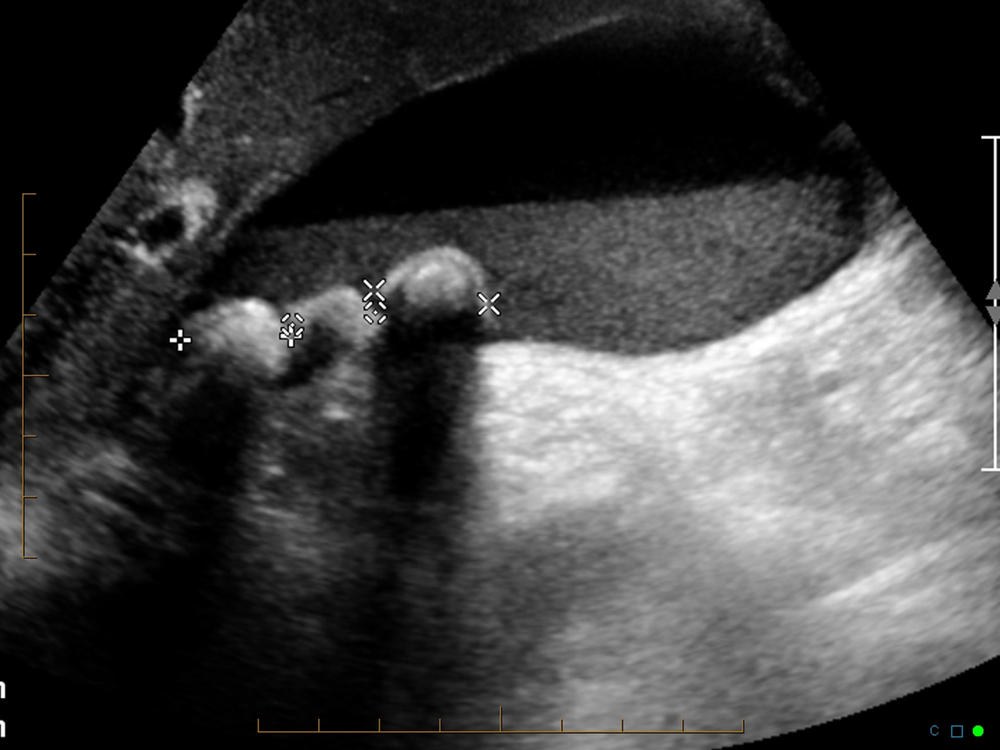

Θα συνεχίσουμε το παραμύθι μας από εκεί που το αφήσαμε… Σχεδόν. Γιατί τελευταία φορά που εξιστορούσα το μύθο των Αυγών του Δράκου, τίποτα δεν είχε αρχίσει ακόμα, και τότε γελάγαμε ακόμα. Και «όποιος γελάει δεν ξέρει ακόμα τη φριχτή αλήθεια», λένε. Μα ας τα πιάσουμε τα πράγματα σιγά σιγά. Όταν ο απαράδεκτος αυτός υπάλληλος του υπέροχου υπέρηχου, που αποκάλυψε πως κουβαλούσα τα αυγουλάκια του δράκου μέσα σε ένα αχλάδι (ποιητικός τρόπος απόδοσης της πάθησης που ονομάζεται κατά ξενέρωτους γιατρούς «χολολιθίαση») οι αγαπητοί γονείς μου, έκλεισαν άμεσα ραντεβού με τον Δόκτωρ Νιόνιο. Μέγιστος χειρούργος και με φήμη Αθηναίζικη καθώς ήταν ο Νιόνιος, ήταν απ’ αυτούς τους γιατρούς που διατηρούν γραφείο επί της Βασιλίσσης Σοφίας, σε μια από τις αείμνηστες πολυκατοικίες με τα τρομερά φουαγιέ. Ε, όπως είδα κι εγώ το ωραίο το φουαγιέ, αποφάσισα να αποτάξω τη γενική μου απέχθεια προς τη δυτική ιατρική, και σαν καλό κορίτσι που είμαι, να ακούσω τη φωνή της λογικής (της μητέρας μου της Ζωής δηλαδή, εγώ είμαι πλήρως παράλογη, κατά πως φαίνεται) και να πάω να με γνωματεύσει ο κύριος Νιόνιος.

Η οικογένεια μας έχει μια ροπή προς κάθε τι παράξενο, ή μάλλον για να το θέσω καλύτερα, τείνουμε να προσκαλούμε κοντά μας, όλο παράξενους ή μισότρελους ανθρώπους και τις αντίστοιχες καταστάσεις που τους ακολουθούν. Καθώς αυτή είναι η κατάσταση μας λοιπόν, δε θα μπορούσαμε παρά να πέφταμε σε συγχωριανό του πατριού μου του Κούκι -από το νησί του την Κεφαλονιά- πράγμα που έδωσε την άνεση στον Δόκτωρ Νιόνιο, αφού μου πετάξει ελαφρά τη καρδία πως η μόνη λύση για την περίπτωση μου είναι η ολική αφαίρεση χολής, να ρωτήσει με ένα nano-second διαφορά, αν ξέρει την τάδε συννυφάδα από την Πέρα Ραχούλα. Εγώ βίωνα τον εσωτερικό μου θάνατο, ο οποίος συνοψιζόταν σε μια από τις πιο μισητές μου λέξεις , «εγχείριση» ενώ οι άλλοι κάνανε chit-chat χαλαροί κι απλωμένοι σε ωραίες βελούδινες πολυθρόνες. Όταν κατάφερα να τους συνεφέρω όλους και να επικεντρωθούμε στο πραγματικό πρόβλημα, άρχισα να κάνω τις χίλιες ερωτήσεις στον γιατρό για το αν υπάρχει εναλλακτική θεραπεία, ποιες οι επιπτώσεις, ποια η διαδικασία και τα λοιπά. Φυσικά και ο γιατρός ως ήτο αναμενόμενο, δήλωσε πως η εγχείριση είναι τόσο ρουτίνας, που η ευκολία της παρομοιαζόταν με το να αλείφεις λιωμένο βούτυρο σε ψωμάκι. Φυσικά, εν τέλει, κατάφερε να με καθησυχάσει απειλώντας με πως αν δεν έκανα την εγχείριση κινδύνευα να πεθάνω από Παγκρεατίτιδα. Το οποίο δεν έψαξα τι είναι για να μην έχω άλλες κρίσεις πανικού.